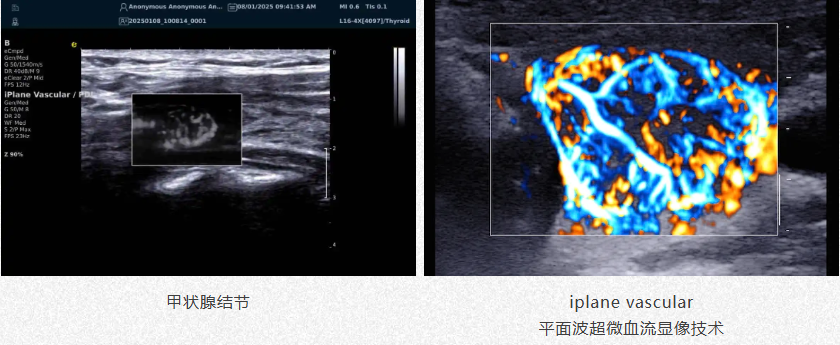

iPlane Vascular

平面波超微细血流显像技术

肿瘤良恶性鉴别

1.高效检测出肿瘤微细血管与低速血流,帮助医生早期发现肿瘤并进行良恶性的鉴别诊断。

2.通过血管指数(VI)定量评估肿瘤内部血管,为诊断提供客观依据。